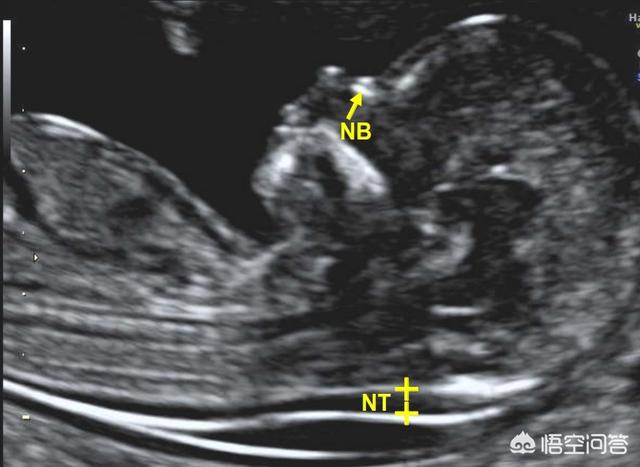

NT检查是B超检查,和普通的B超是一样的,只不过是要测量胎儿颈后透明带的厚度,增加了这一个测量而已。检测的时候会对孕妈妈的腹部扫描,是对胎儿的测量,不是针对孕妈妈的测量,孕妈妈是否空腹,不会影响胎儿的颈后透明带厚度。

1、颈后透明带的厚度和孕周有关系

颈后透明带只有在11周-13周+6天时测量最准确,过早过晚都不好。

2、颈后透明带的厚度和是否有疾病有关系

如果透明带增厚,则暗示胎儿染色体异常、胎儿结构畸形、少见的基因综合征以及自然流产等。如21-三体、18-三体、13-三体异常,先天性心脏病、非免疫 性水肿、颈部囊状淋巴管瘤早期等。